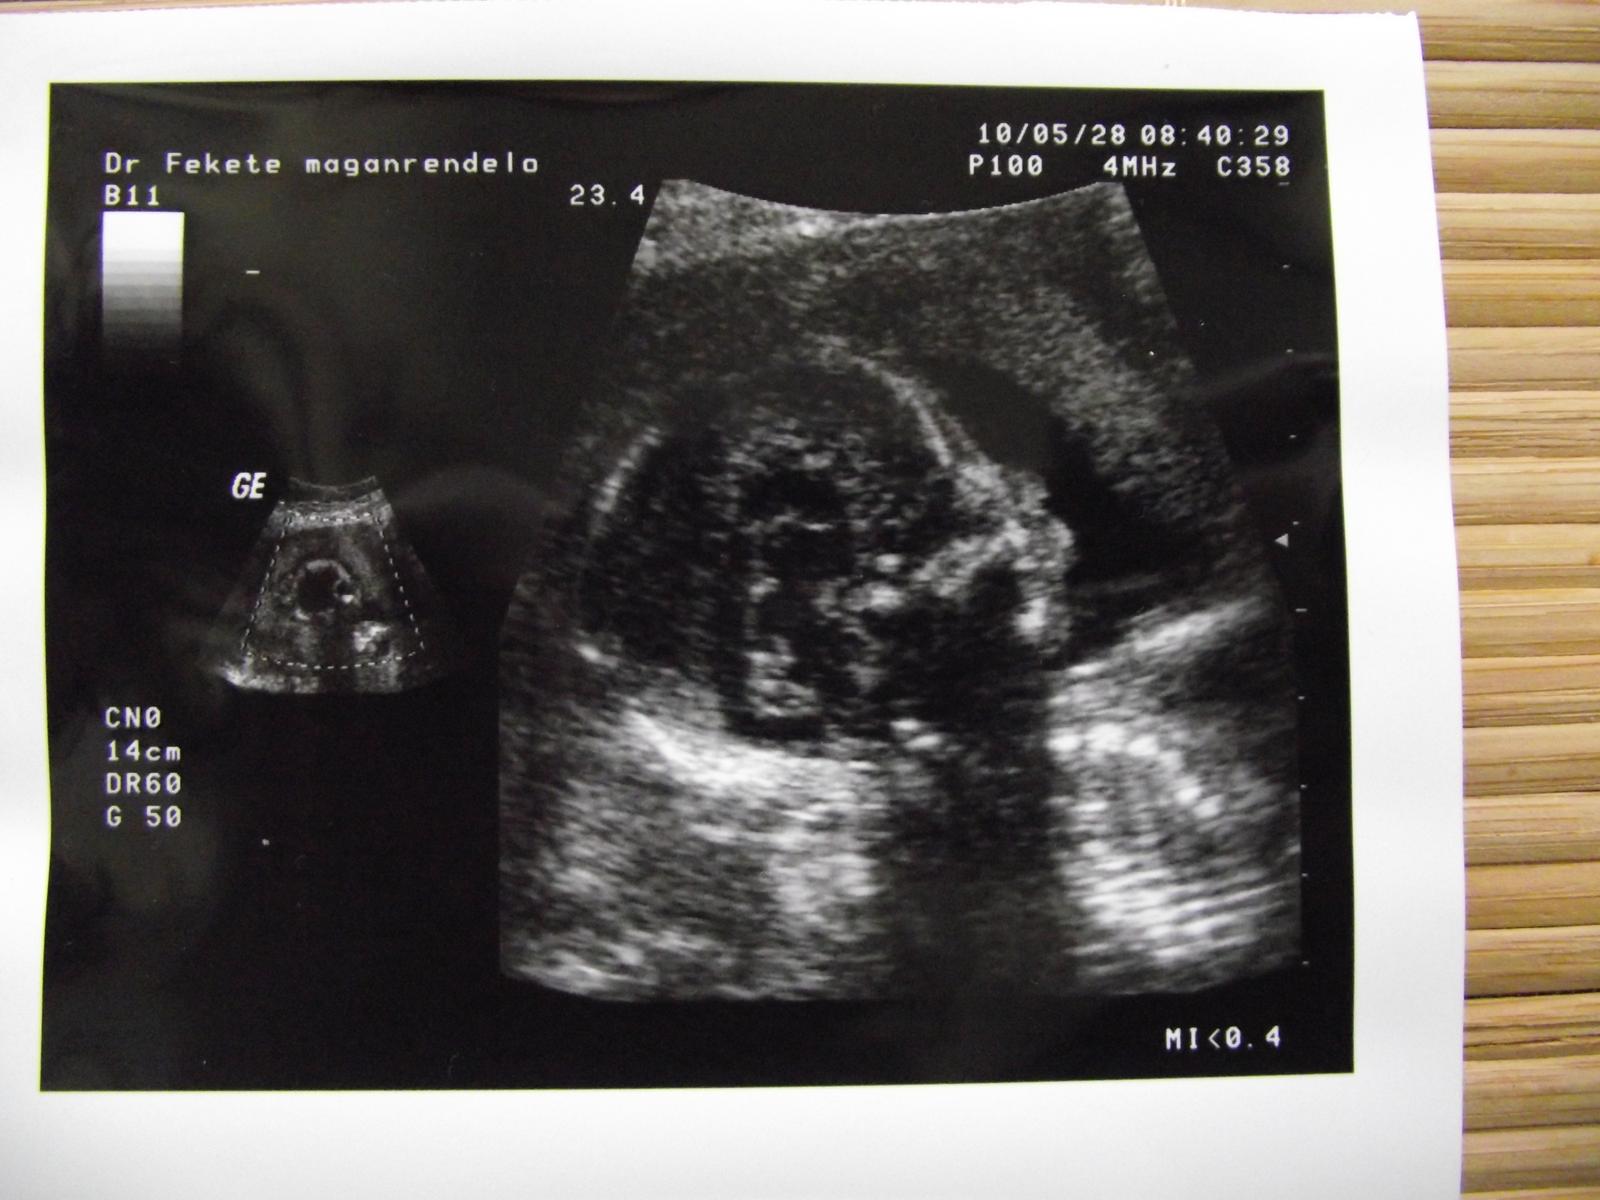

Nas to včera pobavilo to určovanie pohlavia, aj ked prvy lekar sice so spičkovym sonom nam povedal na 80% ze to bude chlapcek ale predsa len v 12 tyzdni tehu .. tento nam uz povedal na 90% ze to bude dievcatko ale aj tak babenko malo nozky pokope a pupocnu snuru medzi nozkami 🙂

19.10. mam dalsiu 3D kontrolu na slovensku a 31.10. mam dalsiu beznu kontrolu v madarku - aspon bude zase na porovnanie, ze ktory lekar mal pravdu 🙂

@rohlicka no draha, to je najlepsia spravicka vcerajska 😀 😀 😀 😉 tesim sa s tebou, ze babenko je zdrave ako repa a kukam, ze uz aj riadne velike 😀 waw, ze 20cm v 18.tt - cim ho krmis? 😀 teda pre srandu kraliciu pridavam dole pribliznu tabulku vyvoja baba v jednotlivych tt. Tak bud je ta tabulka naprd alebo budes mat riadne 5kilove detatko 😀 😉

A dalsia haluska je to, ze tento doki ti povedal,ze to vyzera na dievcatko 😀 A ty si aj chcela, vsak? 🙂 No ale co pocuvam z kazdej strany ako sa lekari pri ultrazvuku mylia, tak este nevedno aky bude konecny verdikt 😀 Ale ved to je jedno. Dolezite je, ze babenko sa ma v brusku ako v bavlnke, je spokojne a maminka sa tiez zachvilu da dokopy, pekne sa vylieci a bude zase vsetko ouki douki 🙂 😉 😉 😉

@horseshoe ja som tiez zostala zaskocena ze uz je take obrovske 🙂 ale v tabulke mas 2 udaje dlzky - dlzku ku kostrci a dlzku s nohami. Kedze vcera meral aj dlzku stehennej kosti predpokladam ze dany udaj je uz aj s nozickami 🙂 co by teoreticky mohlo zodpovedat danej dlzke . lebo podla lekara je vsetko v najlepsom poriadku a zodpoveda babetko danemu tyzdnu 🙂